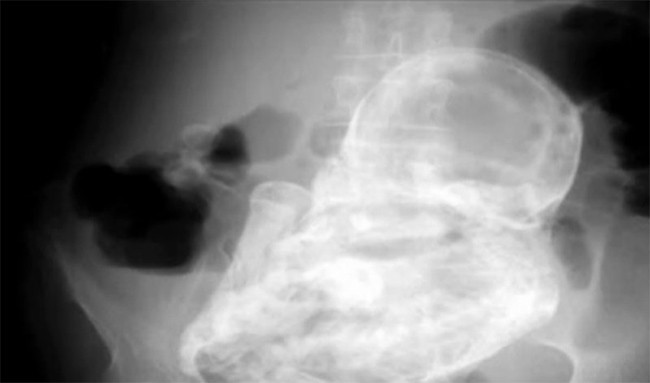

Esa calcificación hace que el feto parezca de piedra, y de igual modo que entonces hablamos de ellos por un caso de dolor abdominal en una mujer mayor, recientemente ha sucedido que una mujer de 82 años acudió al hospital con un cuadro similar, quejándose de dolor de estómago, y una radiografía, la que veis en la imagen, reveló que tenía dentro un bebé de piedra que llevaba con ella 40 años.

El caso que os comentamos hoy ha sucedido en Colombia, en el Hospital de Tunjuelito en Bogotá, al que acudió una mujer de 82 años, aquejada de dolores abdominales, en un cuadro que fue definido, de inicio, como de gastroenteritis. Sin embargo, los doctores que la valoraron notaron algo anormal en el abdomen. En un primer momento sospecharon que podrían ser cálculos biliares, pero luego se decidió llevar a cabo una radiografía y gracias a ella encontraron al bebé de piedra.